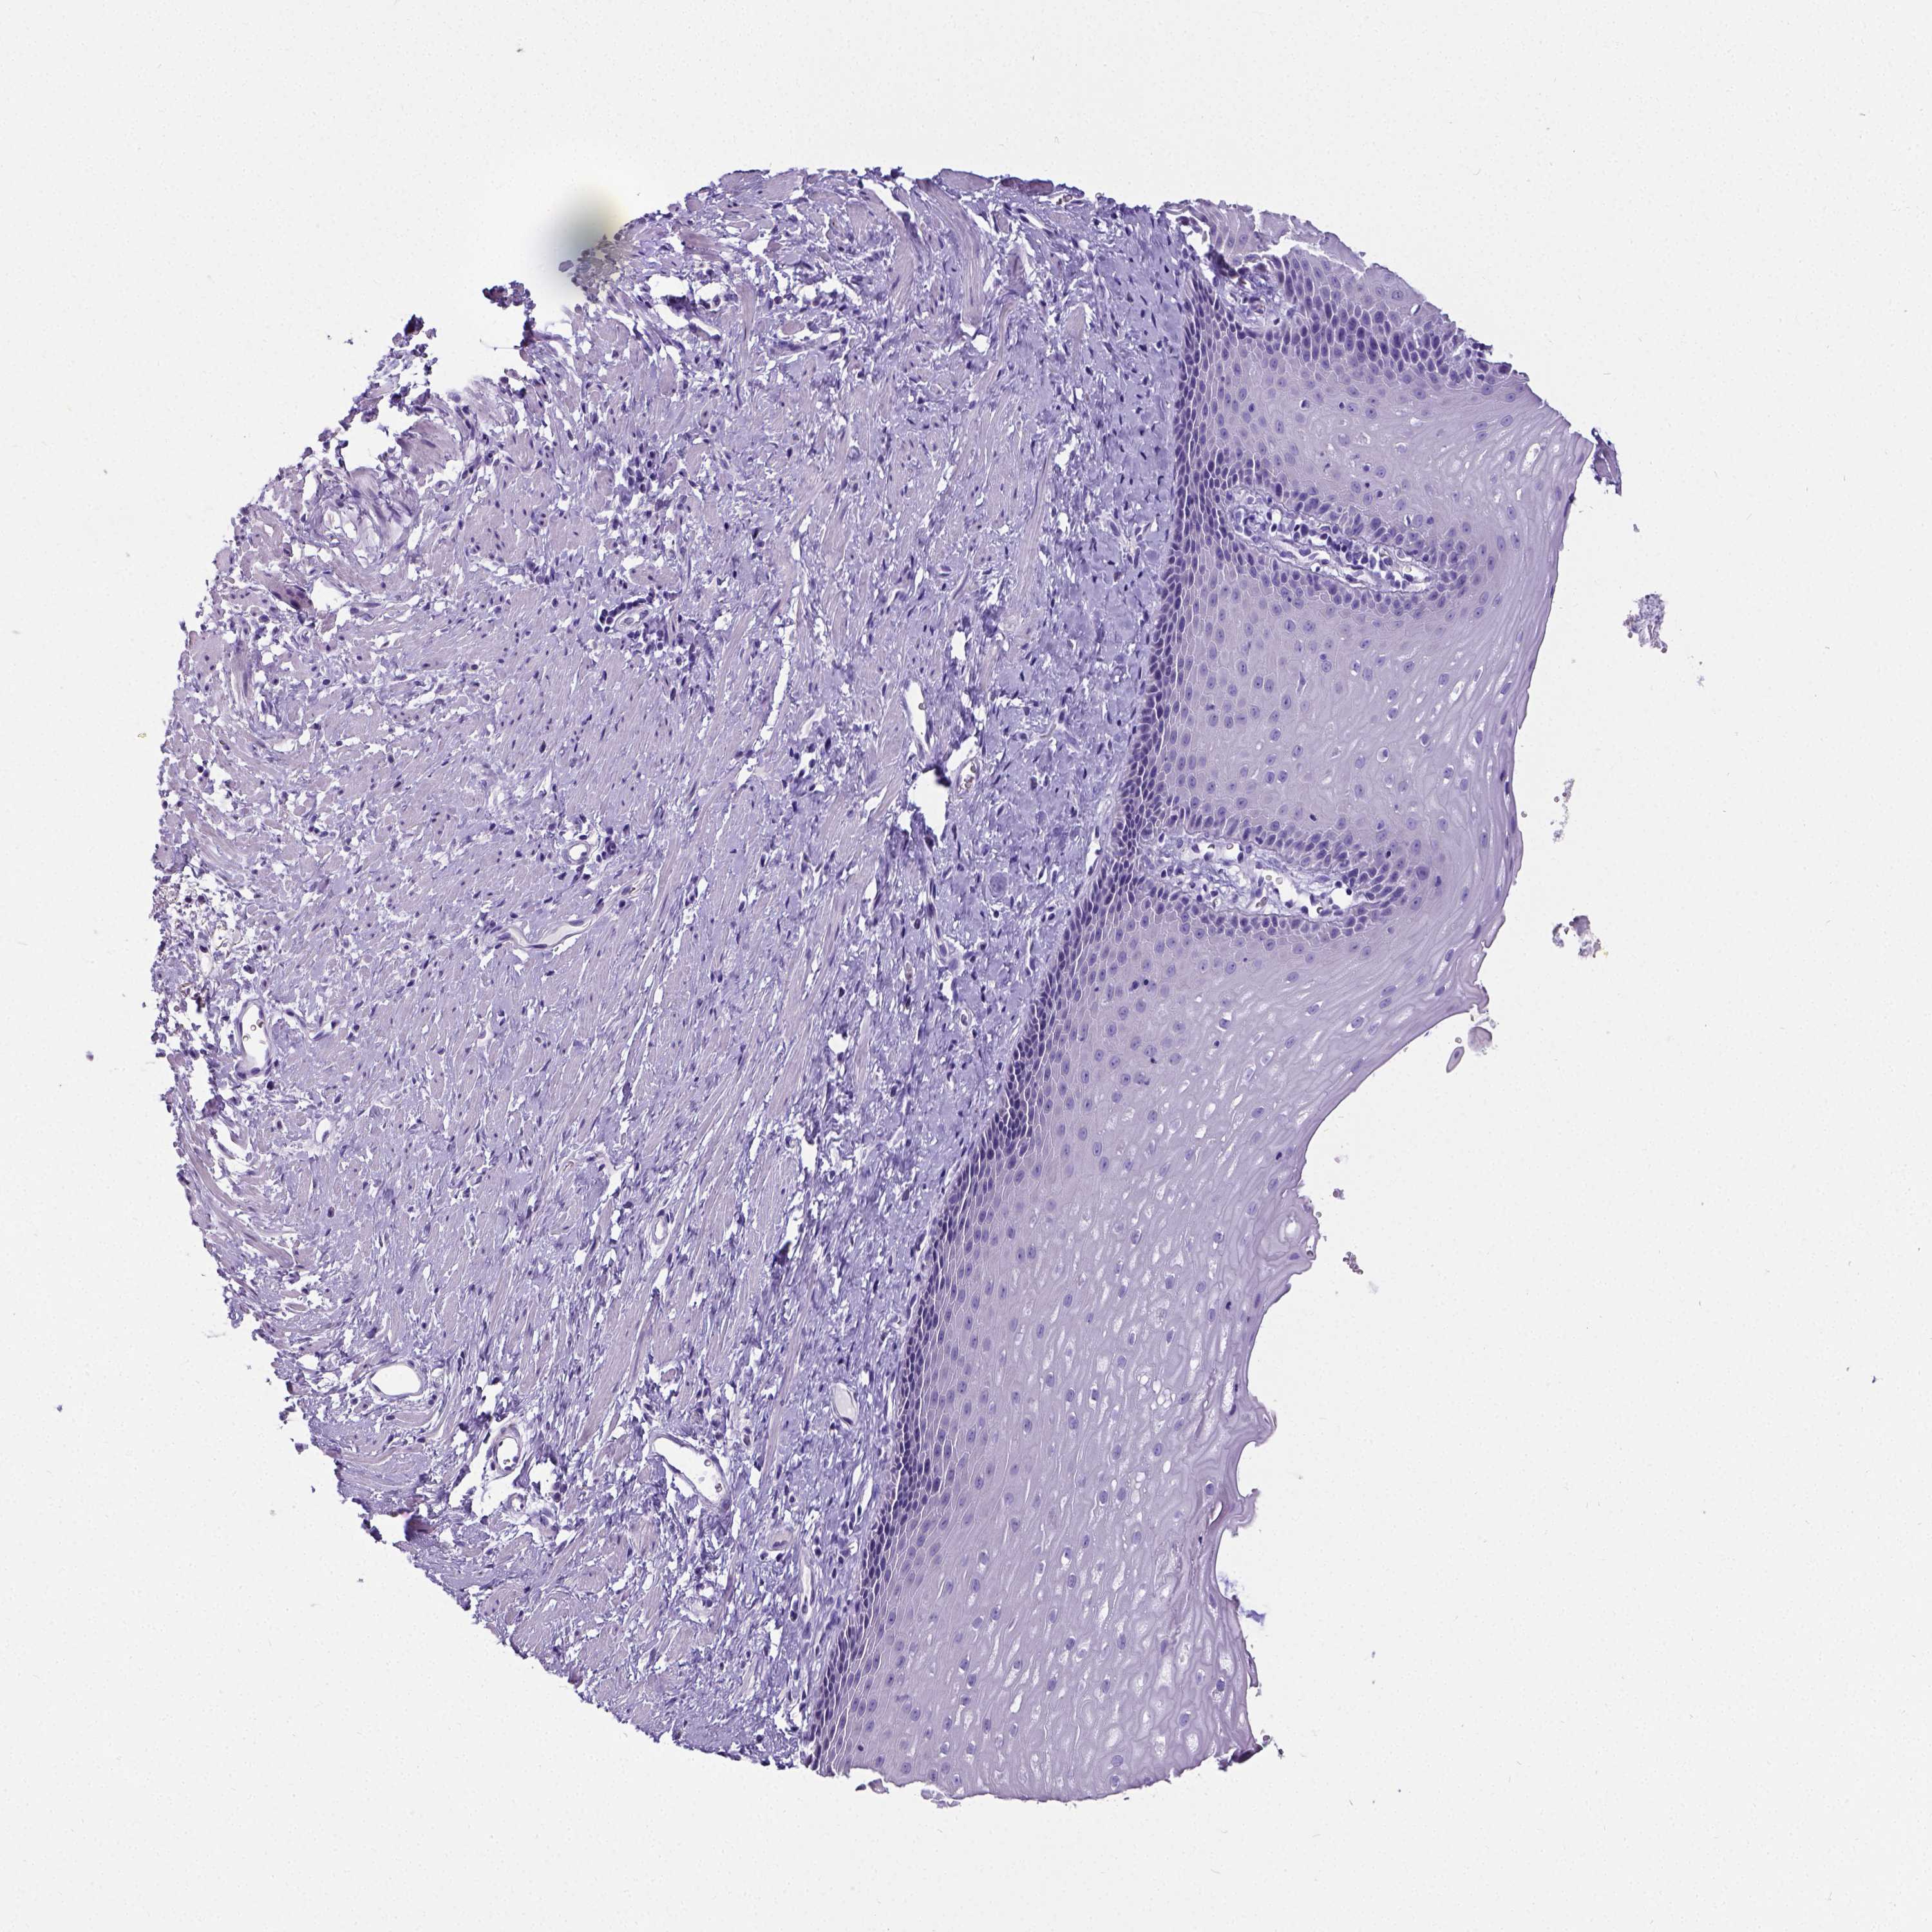

ESOPHAGUS - Antibody stainingi

Antibody staining in the annotated cell types in the current human tissue is reported as not detected, low, medium, or high, based on conventional immunohistochemistry profiling in selected tissues. This score is based on the combination of the staining intensity and fraction of stained cells.

Each image is clickable and will lead to virtual microscopy that enables deeper exploration of all samples and also displays staining intensity scores, fraction scores and subcellular localization as well as patient and tissue information for each sample.

Antibody HPA001042Antibody HPA029543Antibody CAB023669Antibody CAB062562Antibody CAB067751Antibody CAB068229Antibody CAB068230Antibody CAB068231

Squamous epithelial cells Not detectedNot detectedNot detectedNot detectedNot detectedNot detectedNot detectedNot detected